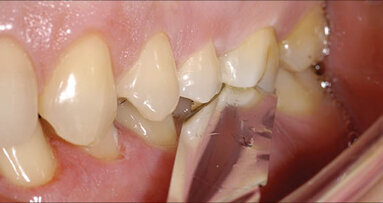

Výroba tzv. šroubovaných korunek a můstků byla vždy omezena osou implantátu. Od tohoto osvobozuje na trhu relativně nový systém „Dynamických bází“. Ten dovoluje vyrobit estetickou korunku, i když by dle osy implantace měl otvor vycházet např. v incizní hraně.

Na základě informací z praxe lze říci, že se jeví jako výhodné využívat naklánění osy = posouvání okluze štoly. Náhrady lékaři přišroubují a tím odpadá dnes hojně zavrhované intraorální cementování a vzniká výhoda snadného sejmutí náhrady v případě potřeby.

Při výrobě náhrad v laboratoři je požadavek na maximální estetiku občas v rozporu s technickými možnostmi danými osou zavedení implantátů. Nutí nás tak ke kompromisům jako jsou cementované náhrady, kde ohrožujeme náhradu nekontrolovaně zatečeným cementem. Osa implantace nás také často nutí nevyrábět náhrady šroubované, avšak nový systém Dynamic Dental nám umožnuje si „vyhrát“ s umístěním otvoru pro šroubek mimo estetickou oblast a vytvořit skutečně vysoce anatomické a estetické náhrady.